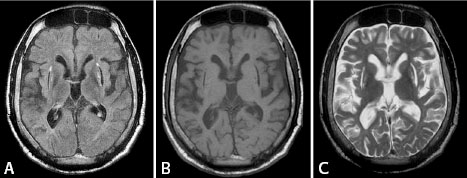

Wilson’s disease showing bilateral putaminal necrosis

and diffuse brain atrophy

Dr. O’Gorman